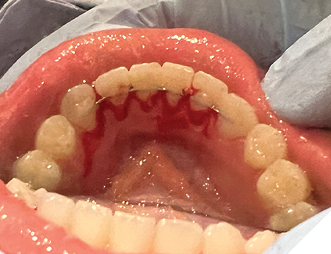

5. Oral hygiene (Fig. 12AB)

Checking for:

i. Bleeding upon probing

ii. Plaque/calculus amount at the gingival of the fixed retainer

iii. Any gingival recession or hyperplastic gingival tissues

Fig. 12A

Fig. 12B